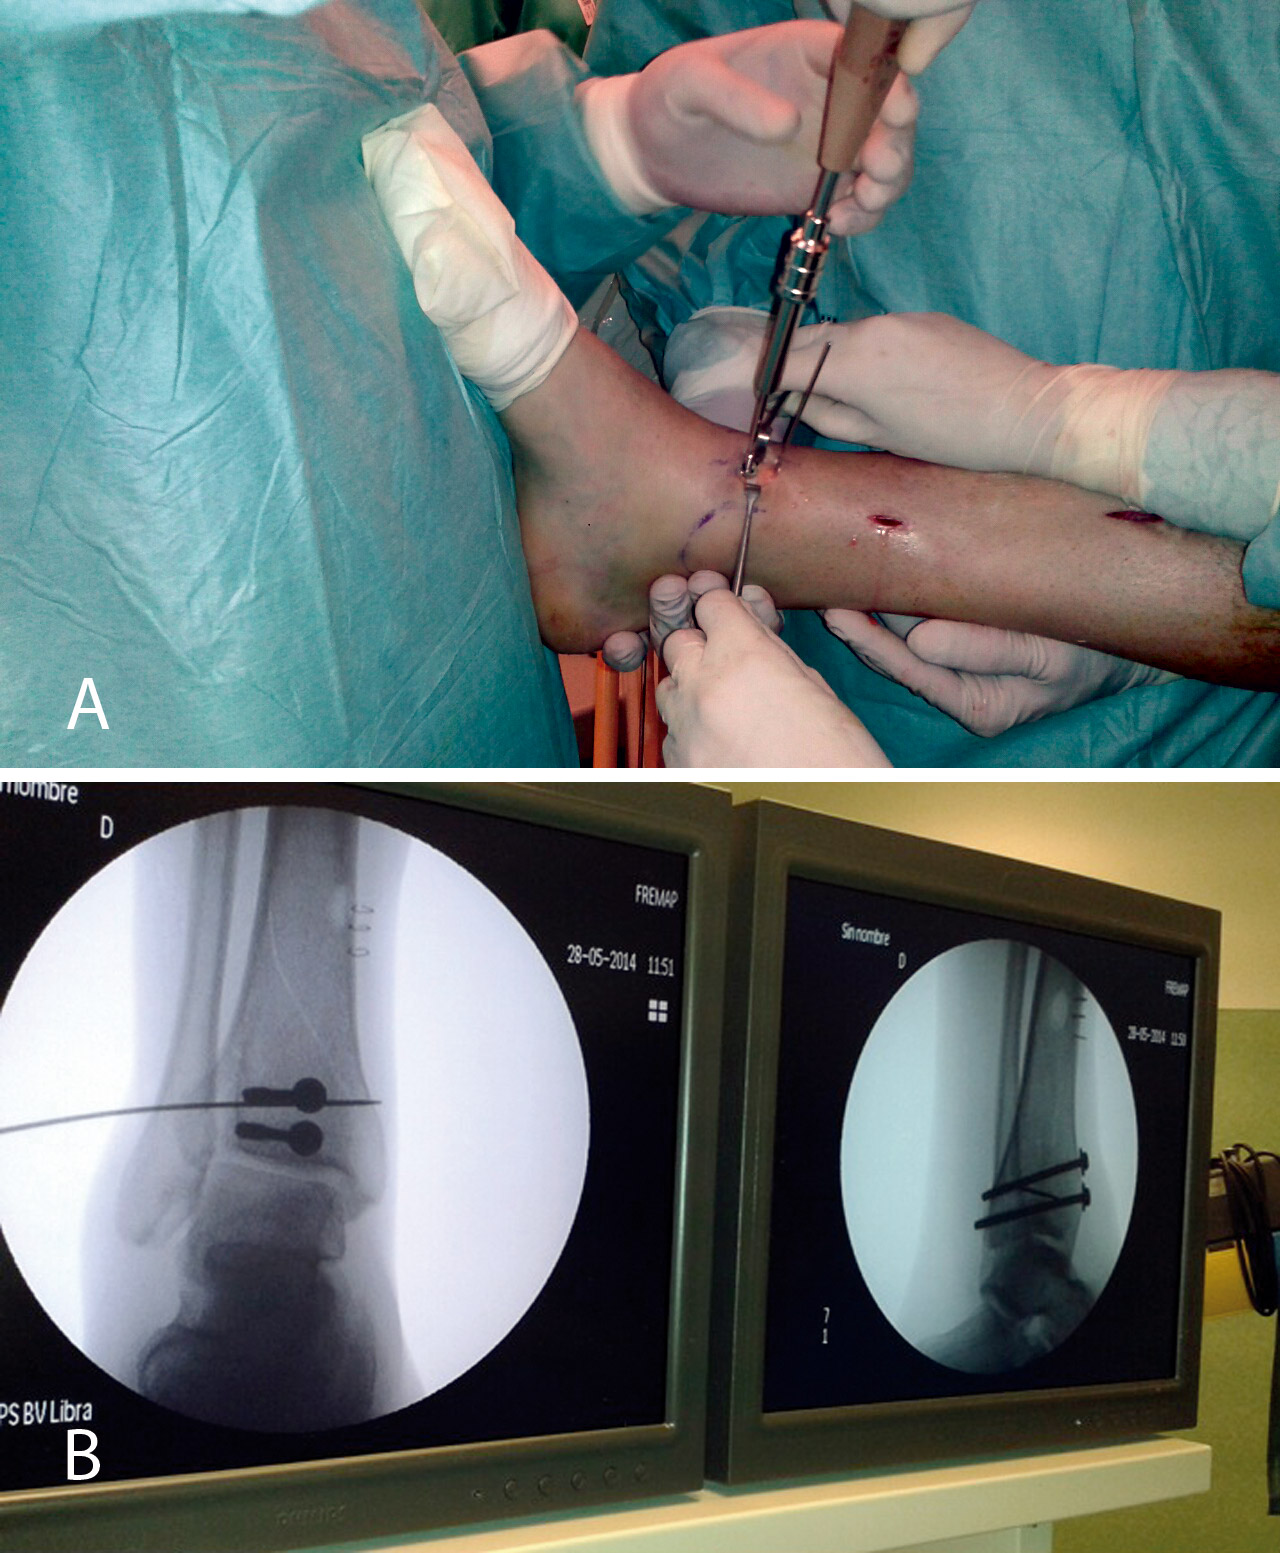

Bajo anestesia raquídea e isquemia en la raíz del miembro afecto, colocamos al paciente en decúbito supino con la pierna en férula de Braun y una tracción en el tobillo con vendas o con sistema de tracción suministrado por casas comerciales.

Realizamos los portales artroscópicos habituales en función de la situación de los extremos óseos de la fractura y practicamos un procedimiento idéntico al anterior: lavado, desbridamiento e identificación del foco de fractura (Figuras 12 a 16).

Figura 12. Caso 2: fractura espiroidea con afectación articular. Posicionamiento en férula de Braun. Tracción con vendas. Realización de portales.

Figura 13. Posteriormente, realizamos la limpieza del foco con cucharilla y la reducción del mismo mediante pinzas de cóndilo bajo control radioscópico/artroscópico, y fijación provisional con agujas de Kirschner.

Figura 14. A continuación, se realiza la medición y colocación secuencial de los tornillos.

Figura 15. Por último, se procede a la colocación definitiva de los tornillos.

Figura 16. Resultado final a los 4 meses.